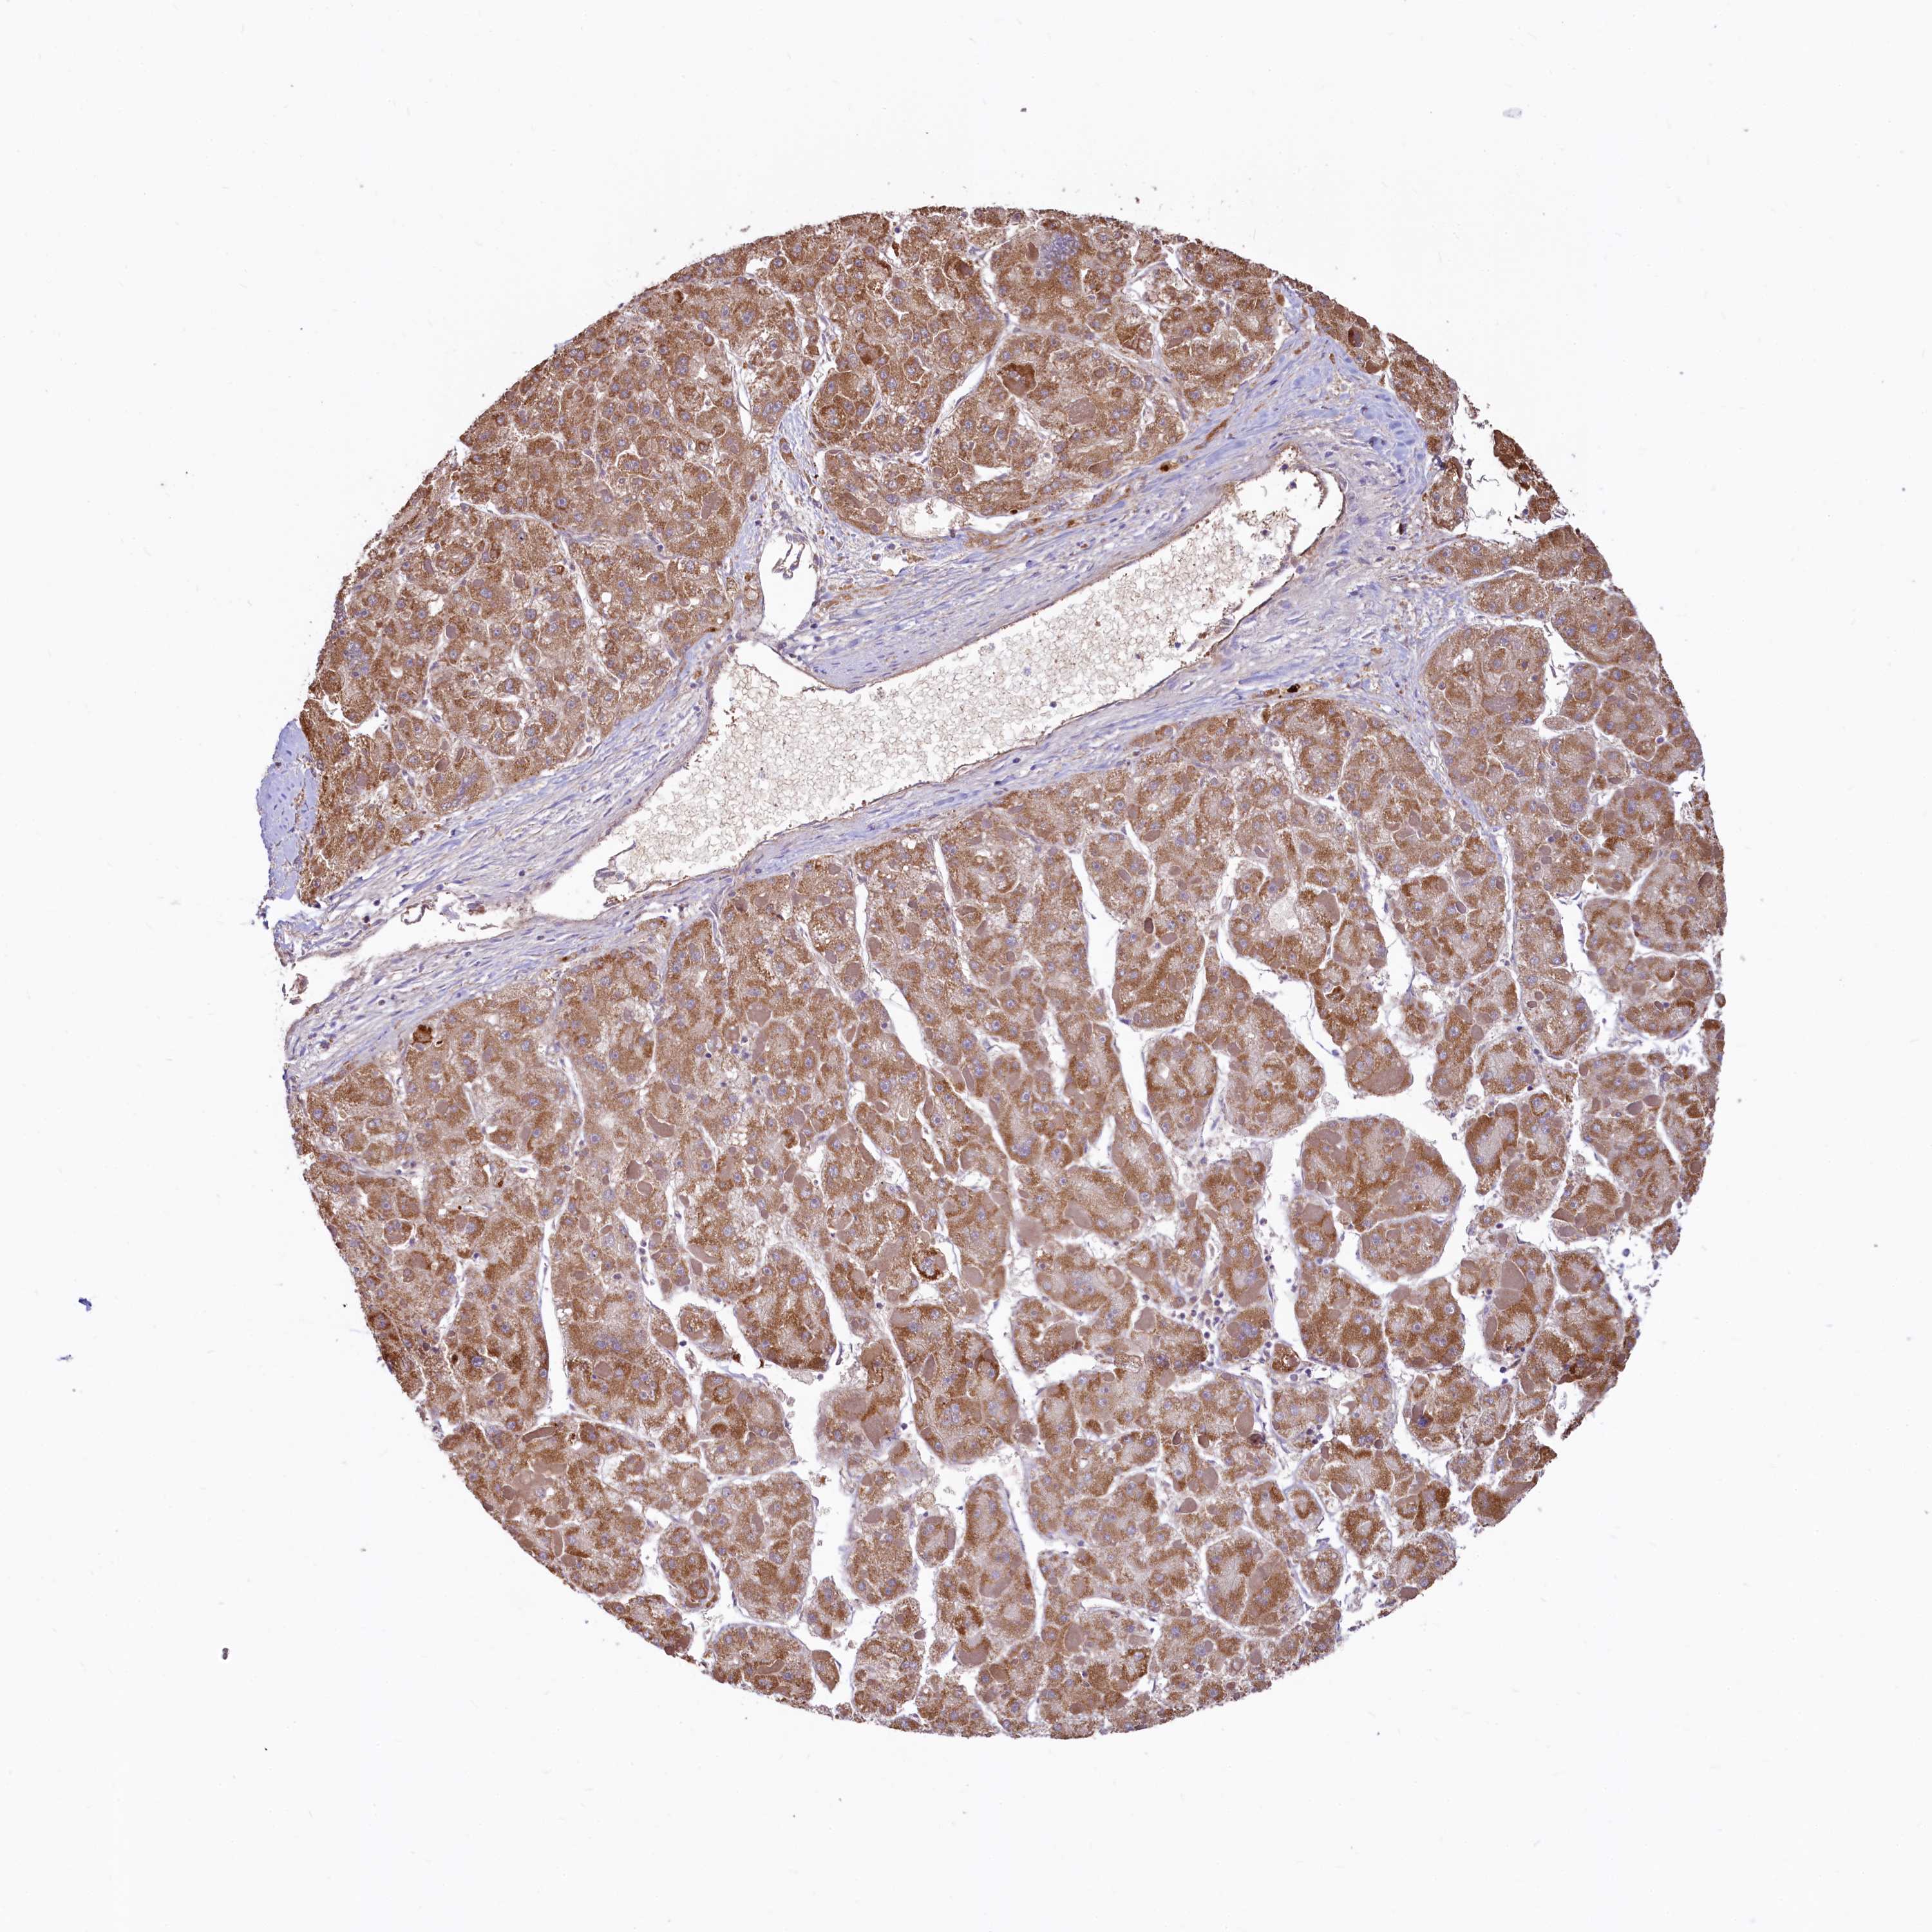

LIVER CANCER - Protein expressioni

A mouse-over function shows sample information and annotation data. Click on an image to view it in a full screen mode. Samples can be filtered based on level of antibody staining by selecting one or several of the following categories: high, medium, low and not detected. The assay and annotation is described here.

Note that samples used for immunohistochemistry by the Human Protein Atlas do not correspond to samples in the TCGA dataset.

Antibody stainingi

Antibody staining in the annotated cell types in the current human tissue is reported as not detected, low, medium, or high, based on conventional immunohistochemistry profiling in selected tissues. This score is based on the combination of the staining intensity and fraction of stained cells.

Each image is clickable and will lead to virtual microscopy that enables deeper exploration of all samples and also displays staining intensity scores, fraction scores and subcellular localization as well as patient and tissue information for each sample.

Antibody HPA040401

Antibody HPA043921

Staining

High

Medium

Low

Not detected

Intensity

Strong

Moderate

Weak

Negative

Quantity

>75%

75%-25%

<25%

None

Location

Nuclear

Cytoplasmic/membranous

Cytoplasmic/membranous,nuclear

Cholangiocarcinoma

Carcinoma, Hepatocellular, NOS